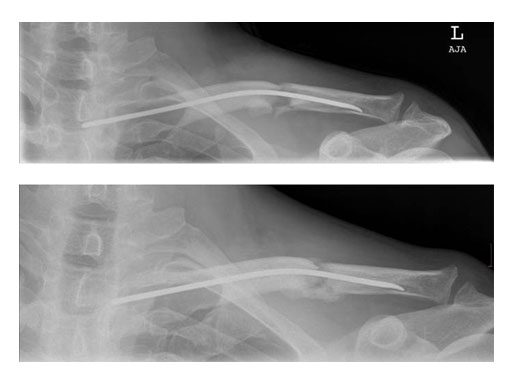

Case 1: Male, 56 years, Bicycle accident

The operative technique as described by Rehm starts with a skin incision just above the sternal end of the clavicle. Approximately one cm lateral to the sternoclavicular joint, a hole is drilled into the anterior cortex. A titanium nail varying in diameter between 2.5 to 3.5 mm is mounted on a universal chuck with T-handle. With oscillating movements the TEN is advanced until it reaches the fracture site. If closed reduction manoeuvres are unsuccessful, an additional skin incision has to be made at the level of the fracture site enabling direct manipulation of the fragments.